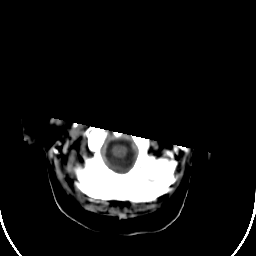

Stroke CT #1 -- Slice #0

[Home][Help][Clinical] Slice 0

Click on sagittal image to select slice. Click on thin tickmark to change timepoint, or thick tickmark for overlay.